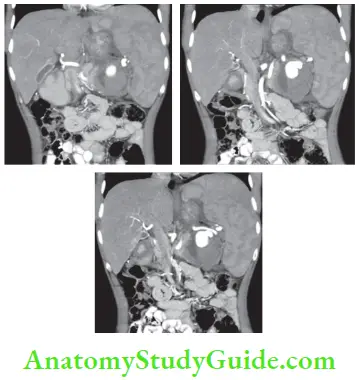

Most of these injuries are diagnosed by CT scan today (CT classification is given).

- CT scan is more reliable. It should be used in cases of doubtful diagnosis and stable patients.1 It also rules out hollow viscus perforation, pancreatic injuries, etc.

Among neoplasms, lymphoma is the most common cause of enlargement of spleen. Spleen used to be removed as a part of a staging laparotomy. Now, it is very rarely removed. Patients with large spleen of chronic myeloid leukaemia, Gaucher’s disease and hairy cell leukaemia (details later) will also benefit from splenectomy.

- Splenectomy is indicated in cases of diagnostic difficulties and in very large spleens.